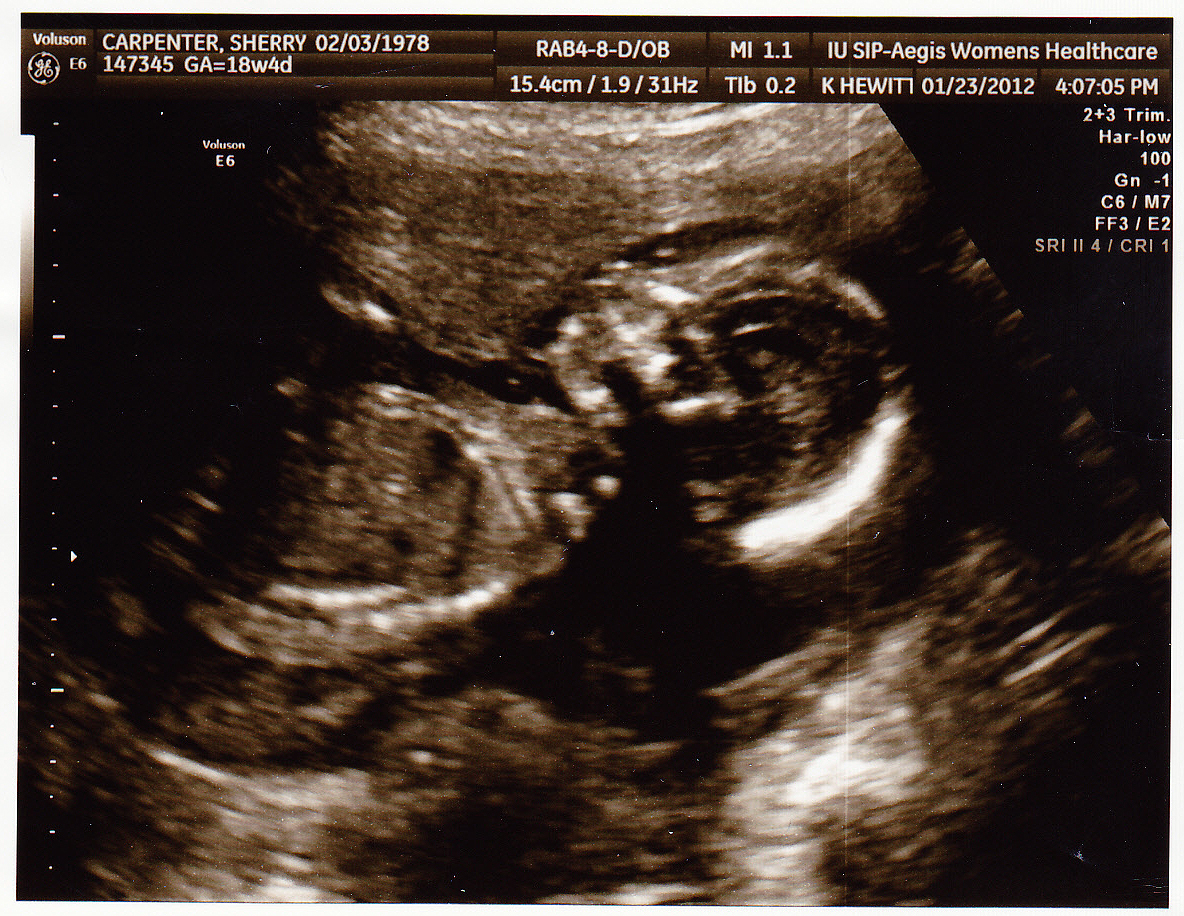

Here are some new ultrasound pictures…

In this 3d picture of her, you can see her hand is open, and she is touching her cheek. No clenched hands. This is a good sign. This is a blurry picture because the ultrasound is trying to filter through the amniotic fluid so it’s impossible to get a perfectly clear picture of her face.